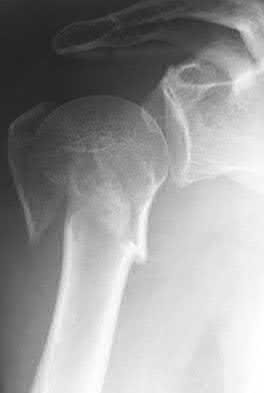

A 22-year-old woman sustains the injury seen in Figure 12 as a result of a motor vehicle crash. What factor is most closely associated with development of osteonecrosis?

- Reduction quality

- Time from injury to surgery

- Presence or absence of a capsulotomy

- Type of implant used for internal fixation

-

Location of the fracture within the femoral neck Corrent answer: 1

A displaced femoral neck fracture in a young patient is considered a surgical urgency and prompt anatomic reduction and internal fixation is recommended. There are a few studies that have specifically looked at the rate of osteonecrosis in this patient population. A review of femoral neck fractures in patients ages 15 to 50 years revealed that the incidence of osteonecrosis in displaced fractures was 27% compared with 14% in nondisplaced fractures.

The quality of the reduction also influenced the rate of osteonecrosis. Time to reduction, type of implant, presence or absence of capsulotomy, and location of the fracture are not associated with osteonecrosis risk.